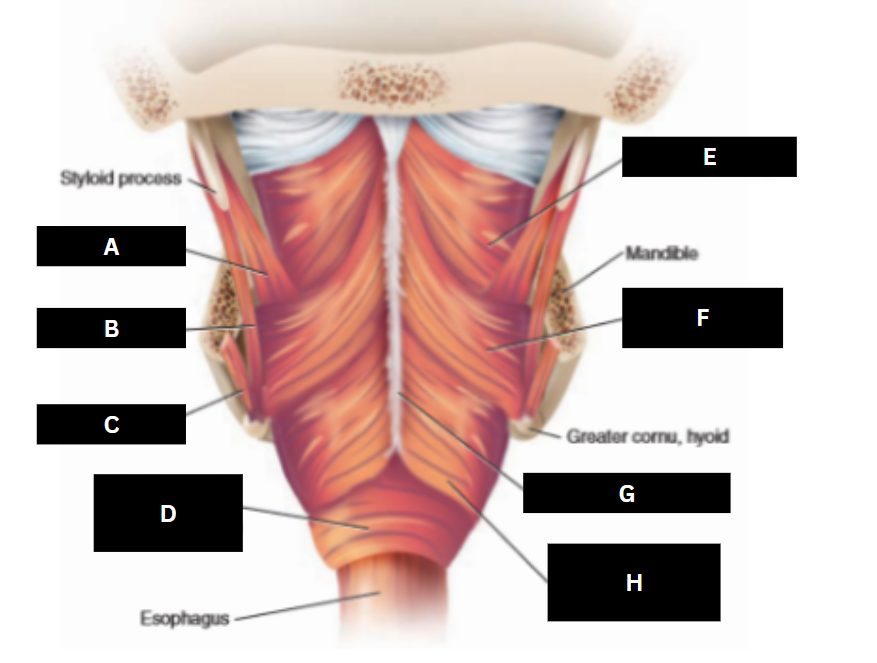

Stylopharyngeus

A

Styloglossus

B

Stylohyoid

C

Cricopharyngeus

D

Superior pharyngeal constrictor

E

Middle pharyngeal constrictor

F

Pharyngeal raphe

G

Inferior pharyngeal constrictor

H